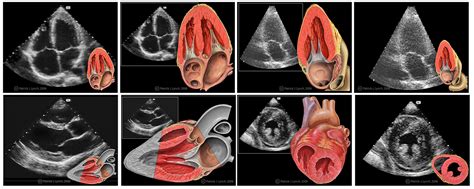

The Different Echo Views: A Look Inside Your Heart

Now, let’s get into the nitty-gritty of the different echo views that cardiologists and sonographers use to get a complete picture of your heart. When you have an echocardiogram , the sonographer doesn’t just take one picture; they systematically move the transducer to capture various angles, each designed to highlight specific structures and functions. Imagine trying to understand a complex machine by only looking at one side – you wouldn’t get the full story, right? The same applies to your heart. These different cardiac ultrasound views are standardized, meaning doctors around the world use the same angles and names, which ensures consistency and makes it easier to compare results. By examining your heart from multiple perspectives, the medical team can thoroughly assess all four chambers, the major blood vessels, and all four valves. Each view has its own unique purpose, focusing on different parts of the heart and helping to identify particular issues. It’s a bit like having a map with different overlays, where each layer reveals more specific details. We’re going to walk through the most common and crucial heart echo views , explaining what each one shows and why it’s so important. Get ready to explore the fascinating architectural details of your heart, chamber by chamber, valve by valve, and vessel by vessel. This detailed exploration is what allows healthcare providers to piece together a comprehensive understanding of your heart’s health, ensuring no stone is left unturned in their diagnostic quest. Understanding these perspectives will truly deepen your appreciation for the diagnostic power of an echocardiogram .

Parasternal Long-Axis View (PSLA): The Initial Glimpse

The Parasternal Long-Axis View (PSLA) is often the very first image a sonographer captures, and it’s a foundational heart echo view because it offers a fantastic, sweeping perspective of several key cardiac structures. To get this view, the transducer is typically placed on your chest, just to the left of your sternum (breastbone), usually around the second or third intercostal space. Imagine a slice through your heart, running from your shoulders down to your hips – that’s essentially the plane the PSLA view shows. This particular cardiac ultrasound view is invaluable for assessing the left ventricle (your heart’s main pumping chamber), the left atrium , the aortic root , and the mitral valve and aortic valve . You can literally see the left ventricle contracting, the mitral valve leaflets opening to let blood flow from the left atrium to the left ventricle, and then the aortic valve opening to allow blood to exit the left ventricle into the aorta, the body’s largest artery. Doctors use this view to measure the size of the left ventricle and left atrium, which helps identify enlargement, a common sign of various heart conditions like high blood pressure or heart failure. They also critically evaluate the function of both the mitral and aortic valves, looking for problems such as stenosis (narrowing) or regurgitation (leakage). For instance, if the mitral valve isn’t closing properly, you might see a jet of blood flowing backward into the left atrium during ventricular contraction, a clear sign of mitral regurgitation . The PSLA view is also excellent for detecting fluid buildup around the heart, known as a pericardial effusion . Because it provides such a broad and clear picture of these critical components, the Parasternal Long-Axis View is an essential starting point for any comprehensive heart echo examination , laying the groundwork for further, more detailed assessments. Its clarity and wealth of information make it one of the most frequently used and informative echo views .

Parasternal Short-Axis View (PSSA): Cross-Sections Revealed

Following the PSLA, the Parasternal Short-Axis View (PSSA) is another absolutely critical heart echo view that gives doctors a completely different yet equally informative perspective. Instead of a longitudinal slice, this view provides cross-sectional images, almost like looking at a loaf of bread sliced horizontally. The sonographer achieves this by rotating the transducer 90 degrees clockwise from the PSLA position. By subtly tilting the transducer, they can capture various levels of the heart, from the base (near the great vessels) to the apex (the bottom tip of the heart). This allows for a detailed examination of the ventricles in cross-section and the heart valves at different levels . One of the most important images derived from the PSSA view is the assessment of the left ventricular wall motion . You can see the entire circumference of the left ventricle contracting, which is crucial for identifying areas of the heart muscle that might not be moving properly due to conditions like a previous heart attack (myocardial infarction) or ischemia (reduced blood flow). The PSSA also offers excellent visualization of all three leaflets of the aortic valve , which is invaluable for detecting congenital abnormalities or acquired diseases like calcification. Furthermore, at a slightly lower level, it perfectly shows the mitral valve as a